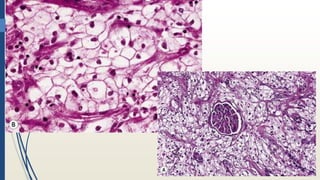

Histopatología

1. Red vascular FINA

• Separa las células de carcinoma en alveólos

2. Patrón SOLIDO-ALVEOLAR DE

CRECIMIENTO

3. Celulas claras

• POR CONTENIDO DE GLUCÓGENO Y LÍPIDO

Chromophobe renal cell carcinoma. This shows the two cell

types consisting of the small eosinophilic cells, which usually

have perinuclear halos, and the large pale (but not clear)

chromophobe cells. The two cell types are usually admixed but

occasionally, as seen here, the chromophobe cells line up along

the blood vessels

Chromophobe renal cell carcinoma. Some tumors consist

entirely of the pale chromophobe cells. The cell membranes are

quite conspicuous, and it can be noted that this is not a clear

cell lesion.